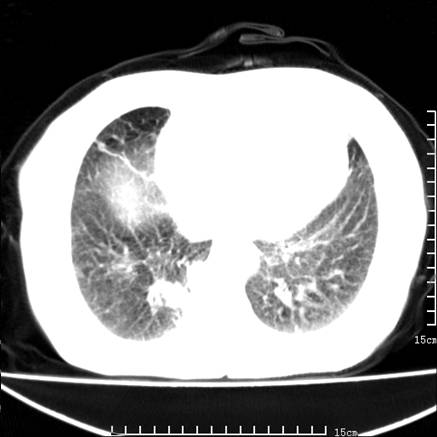

女,王某,58岁,咳嗽三个月余,基层医院二个月前诊为肺结核,用抗结核药二个月无明显疗效。

心包积液致肺瘀血.右侧周围型肺癌伴肺内转移,中间裂积液,叶间胸膜肥厚.右上肺大泡,右侧胸膜肥厚.

双肺继发型tb,心功能不全并肺淤血、心包、双侧叶间裂积液,肺大泡,右下胸膜肥厚钙化。